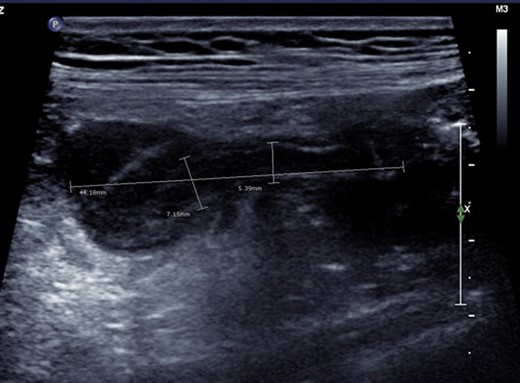

On examination, the patient was afebrile and haemodynamically stable. Abdominal palpation revealed tenderness in the right iliac fossa with voluntary guarding, percussion and rebound tenderness. Neither bimanual nor speculum examination was performed. Blood tests demonstrated leukocytosis (11.6 × 109/L), neutrophilia (8.63 × 109/L; 75%) and mildly elevated C-reactive protein (9.6 mg/L). Beta-human chorionic gonadotropin was appropriate for gestational age (23 000 IU/L). Urine analysis was unremarkable. Ultrasound confirmed a viable intrauterine pregnancy, an inflamed appendix and surrounding free fluid. This was thought to represent acute appendicitis with perforation (Fig. 1).

Ultrasonographic appearance of the right iliac fossa. An ill-defined hypoechoic region surrounding a tubular non-compressible structure (maximum calibre 7.15 mm) was identified. This appearance was thought most likely to represent perforated appendicitis with no definable walled-off collection.